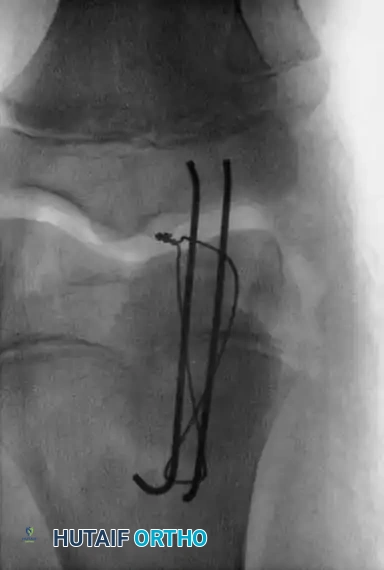

4. Internal Fixation (Tension Band Principle)

* Drive two parallel, longitudinal Steinmann pins (or heavy Kirschner wires) from distal to proximal across the fracture site.

* Leave the pins protruding approximately 0.5 cm (1/4 inch) distally to facilitate future removal.

* Pass a flexible stainless-steel wire (18- or 20-gauge, depending on patient size) transversely through the insertion of the quadriceps tendon at the superior pole.

* Pass the wire distally, crossing it in a figure-of-eight fashion over the anterior surface of the patella.

* Pass the wire deep to the protruding Steinmann pins at the inferior pole.

- Tighten the tension band wire symmetrically. The tension band converts the tensile forces of the quadriceps into compressive forces at the articular surface during knee flexion.

- Pitfall: Do not overtighten the wire, as this can cause anterior gaping and posterior articular angulation of the cartilaginous fragment.